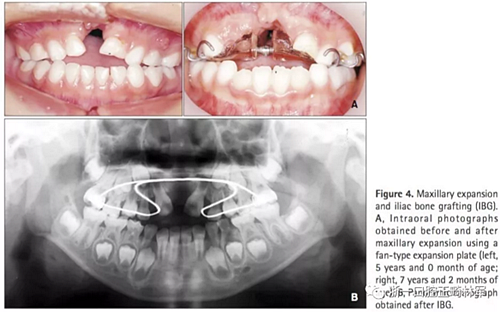

第一階段(圖4及表2)

上頜牙弓使用fan-type擴(kuò)弓器(慢擴(kuò),0.25mm/周)。7歲7月時(shí)行IBG,隨后上頜恒側(cè)切牙與移植區(qū)萌出。